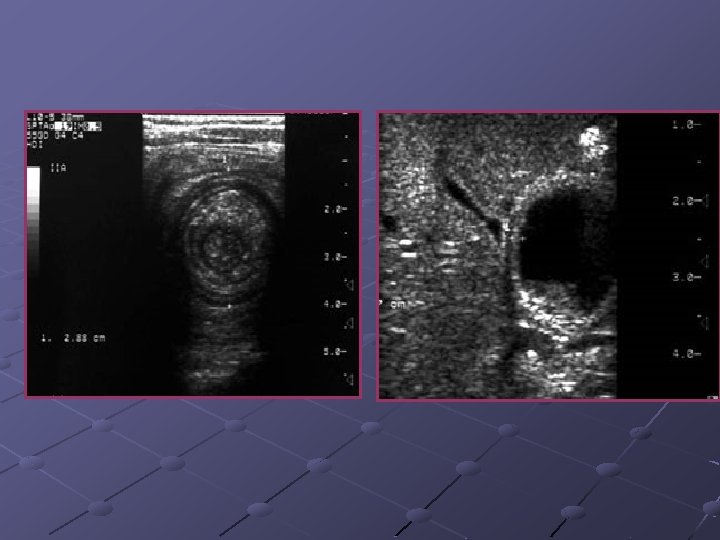

Cas n° 5 17 mois Histoire médicale antérieure = o Pleurs, douleurs abdominales

3, 7 x 2, 8 cm Depuis le rectum hypochondre gauche

INVAGINATION INTESTINALE AIGUE (IIA) Télescopage et penetration d’ un segment intestinal dans le segment d’ aval. Urgence diagnostique et thérapeutique: compression vasculaire ischémie et nécrose Nourrisson ( 80 % entre 6 mois et 2 ans ). Maximum entre 4 et 12 mois (I). Avant 3 mois ou après 5 ans (II). Prédominance masculine ( 3 G/2 F).

Idiopathique ( 90% des cas ): adénolymphite mésentérique(caractère saisonnier ) Secondaire: lymphome digestif, meckel, duplication digestive , polype , purpura rhumatoïde , troubles fonctionnels post chirurgicaux , impactions digestives ( mucoviscidose. . ) Formes anatomiques: iléo-iléale n iléo-colique n Appendico-colique n colo-colique n diam. boudin < 20 mm diam. boudin > 25 mm Diagnostic = échographie et non l’ASP Traitement: - Lavements (air, hydrosoluble, eau) - Chirurgie Contre-indications des lavements: péritonite, choc